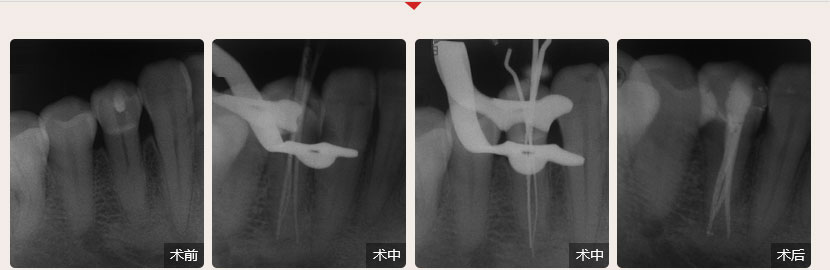

德倫口腔醫生全國根管治療技術競賽獲獎案例展示

根管治療過程